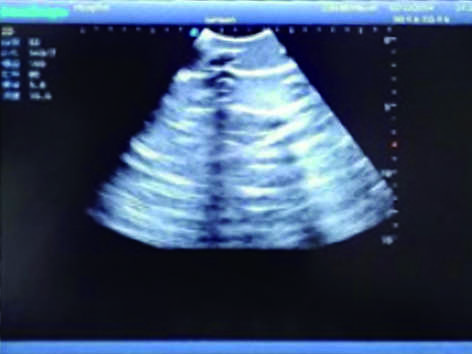

3)  Showing clear and real images of the tissues and organs (including muscle and connective tissue, air-containing lung tissue, pleural structure)

2)  Made of high molecular polymer ultrasound material, close to the real skin. It can conduct ultrasound-guided puncture exercises with various clinical models of real ultrasound machines.